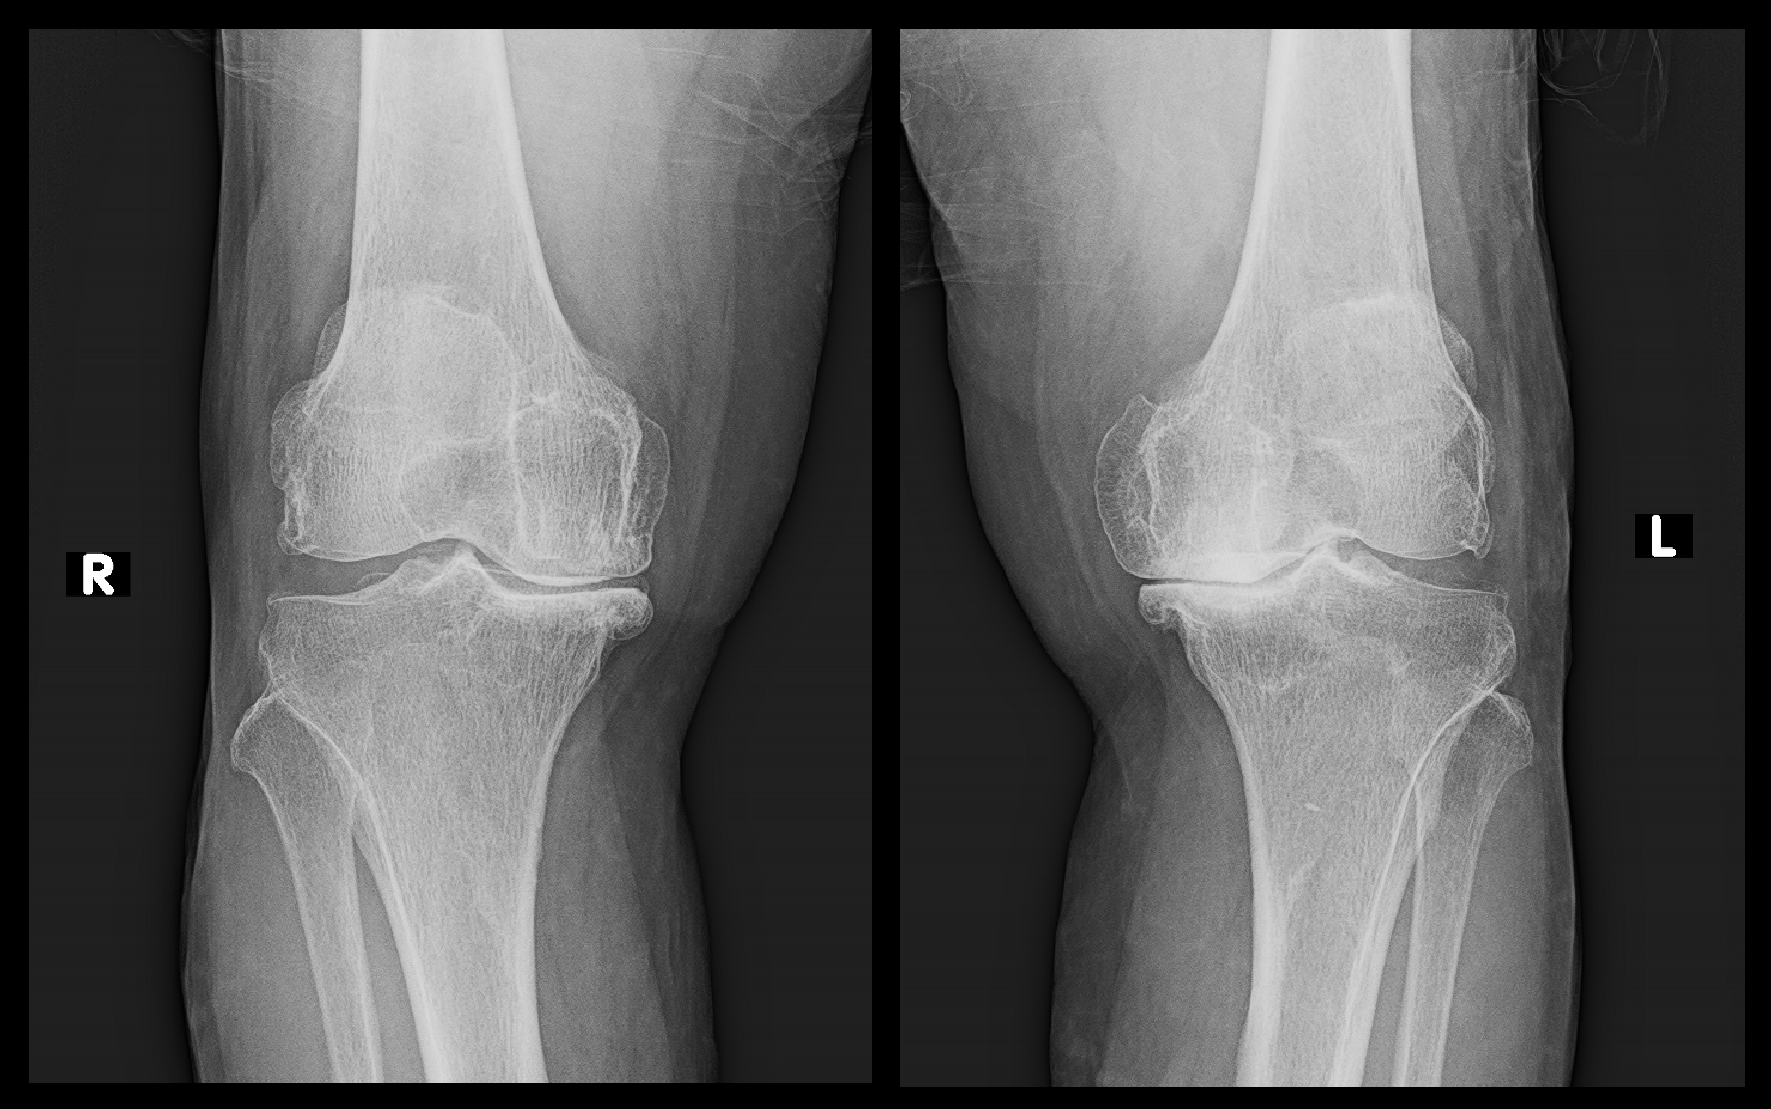

レントゲン像は両側、重度の変形性膝関節症で根本的治療は手術しかないことを説明しつつ、痛みの程度はVAS4程度であるので(VASスケールは部位別の“痛みについて”を参照のこと)、手術適応はあまりないと受け止めました。

両膝Xp.png

前医では投薬のみの治療対応であったので、ヒアルロン酸製剤の関節内注入療法を勧めました。

そして、患者さんの膝の状態からは手術以外ではVAS2~3の獲得であるので(動画で学ぶ“痛みについて”を参照のこと)、現状の治療で期待できる効果はわずかなところであることを説明しています。

6月27日には両膝痛はVAS2~4での評価ですが、患者さんは大分楽になっていると述べています。